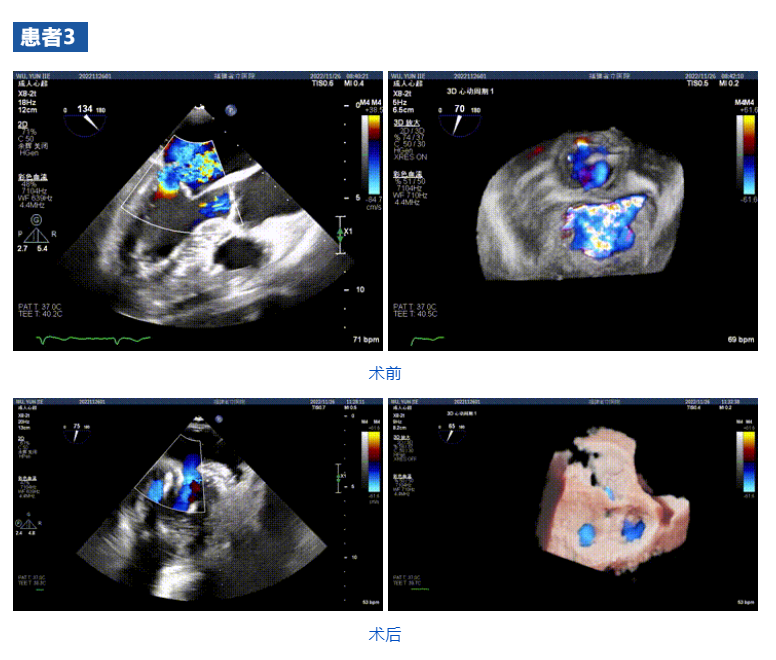

接受治療的三例患者均為器質(zhì)性重度二尖瓣反流(DMR)患者,術(shù)前超聲提示二尖瓣后葉脫垂伴4+反流,左室舒張功能減退。郭延松教授攜同團(tuán)隊(duì)成員陳新敬副教授和洪景宣、方明程、楊清勇主治醫(yī)師、心外科丁杭主任以及超聲科賴寶春、葉振盛主治醫(yī)師共同進(jìn)行病情討論??紤]到患者高齡、基礎(chǔ)疾病多、STS評分高,為外科手術(shù)極高危患者,不適合進(jìn)行外科開胸二尖瓣手術(shù),因此決定為患者實(shí)施經(jīng)導(dǎo)管緣對緣修復(fù)介入術(shù)(JensClip經(jīng)導(dǎo)管瓣膜夾系統(tǒng))。

在浙江大學(xué)醫(yī)學(xué)院附屬第二醫(yī)院王建安教授團(tuán)隊(duì)的支持下,手術(shù)經(jīng)股靜脈-房間隔入路,采用全身麻醉插管,在TEE和DSA引導(dǎo)下完成房間隔穿刺。置入JensClip瓣膜夾系統(tǒng)后,在左房調(diào)整瓣膜夾的位置和軸向,后進(jìn)入左室,在TEE引導(dǎo)下捕捉二尖瓣前后瓣葉,并關(guān)閉瓣膜夾。經(jīng)TEE反復(fù)確認(rèn)手術(shù)效果后最終鎖定并釋放瓣膜夾。術(shù)后即刻超聲顯示瓣膜夾位置穩(wěn)定,功能良好,二尖瓣反流由術(shù)前4+減少至微量,手術(shù)圓滿成功。